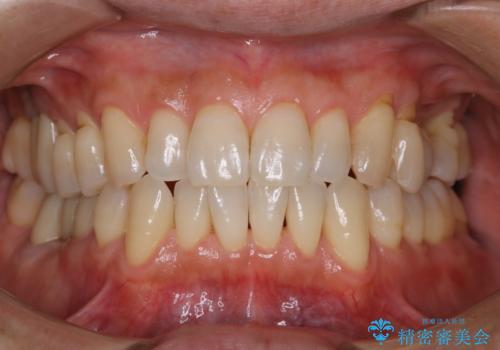

ワイヤー矯正終了時に装置除去と合わせてPMTC

担当医 歯科衛生士